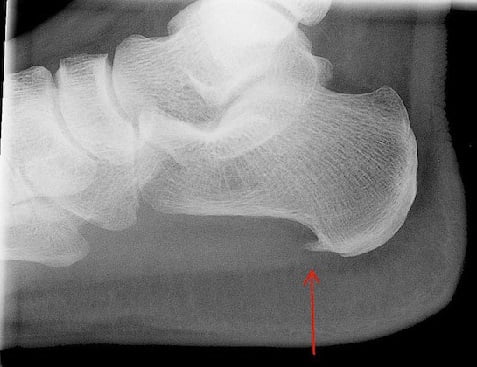

Как выглядит пяточная шпора: фото

На фото ниже показано, как проявляется заболевание у человека.

Пяточную шпору можно заподозрить на основании типичных жалоб на боли при ходьбе и осмотра стопы с прощупыванием пяточной кости. Но для подтверждения диагноза необходимо проведение:

- рентгена стопы с выявлением типичного нароста,